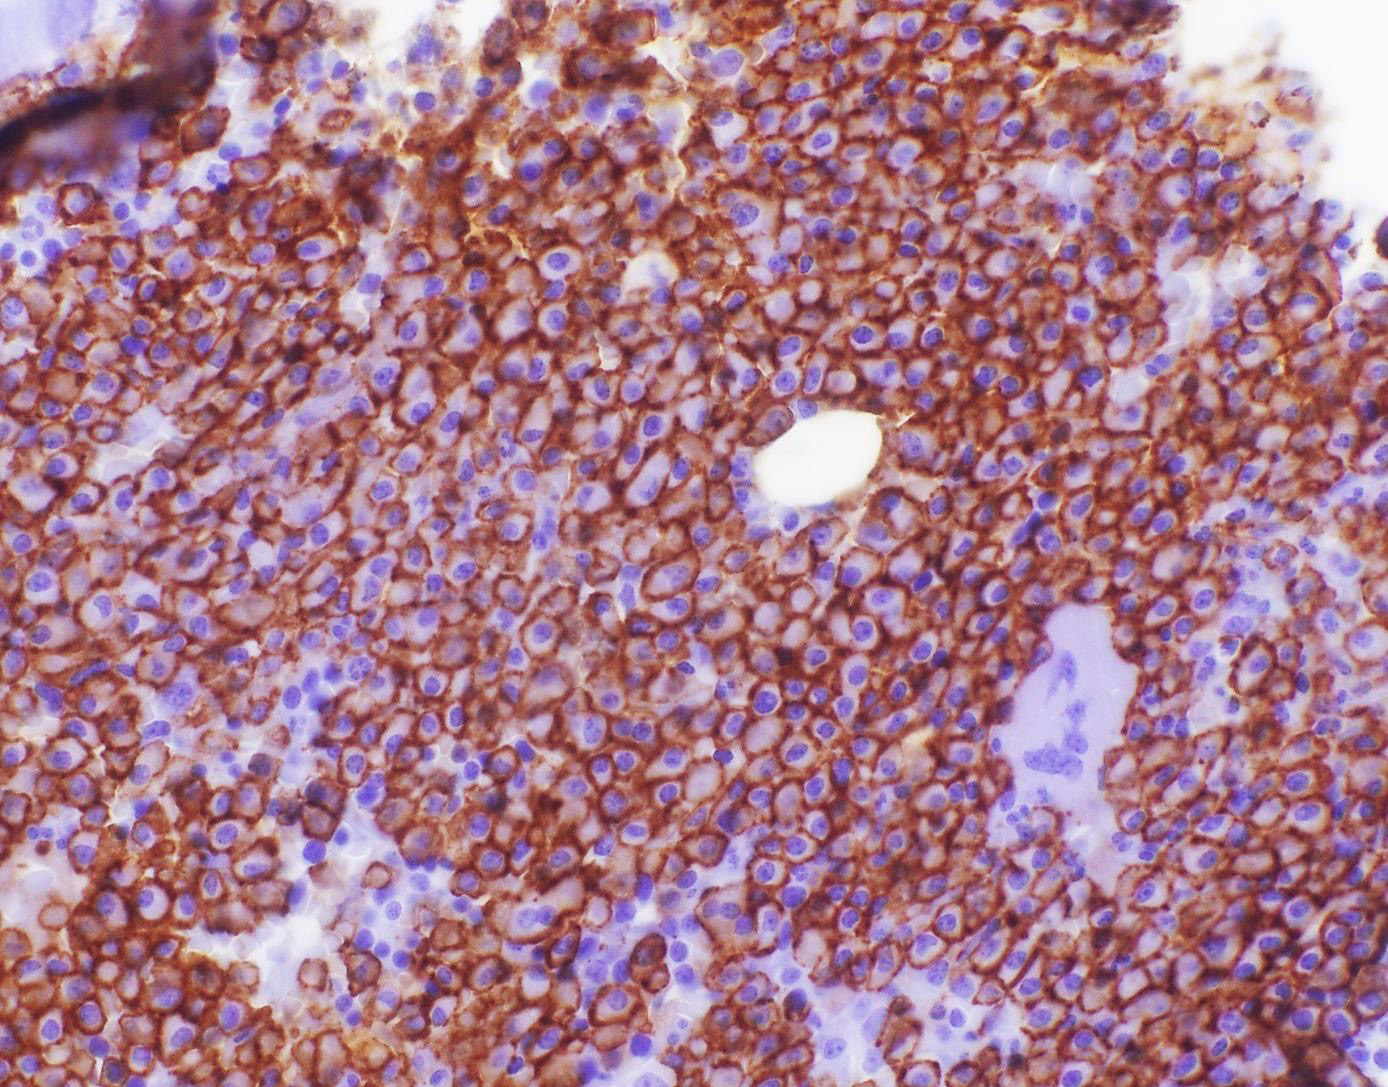

Microscopic (histologic) description

- Core biopsy (Am J Clin Path 1987;87:342):

- Interstitial clusters, nodules or sheets of plasma cells

- Areas of bone marrow may be spared with preserved hematopoiesis, other cases may have diffuse involvement and markedly suppressed hematopoiesis

- Prominent osteoclastic activity may be seen

- IHC to quantify plasma cells (CD138), stains for Ig kappa and lambda to establish clonality

Microscopic (histologic) images

Contributed by Genevieve M. Crane, M.D., Ph.D. and Tapan Bhavsar, M.D., Ph.D.

Positive stains

- CD38, CD138, VS38c